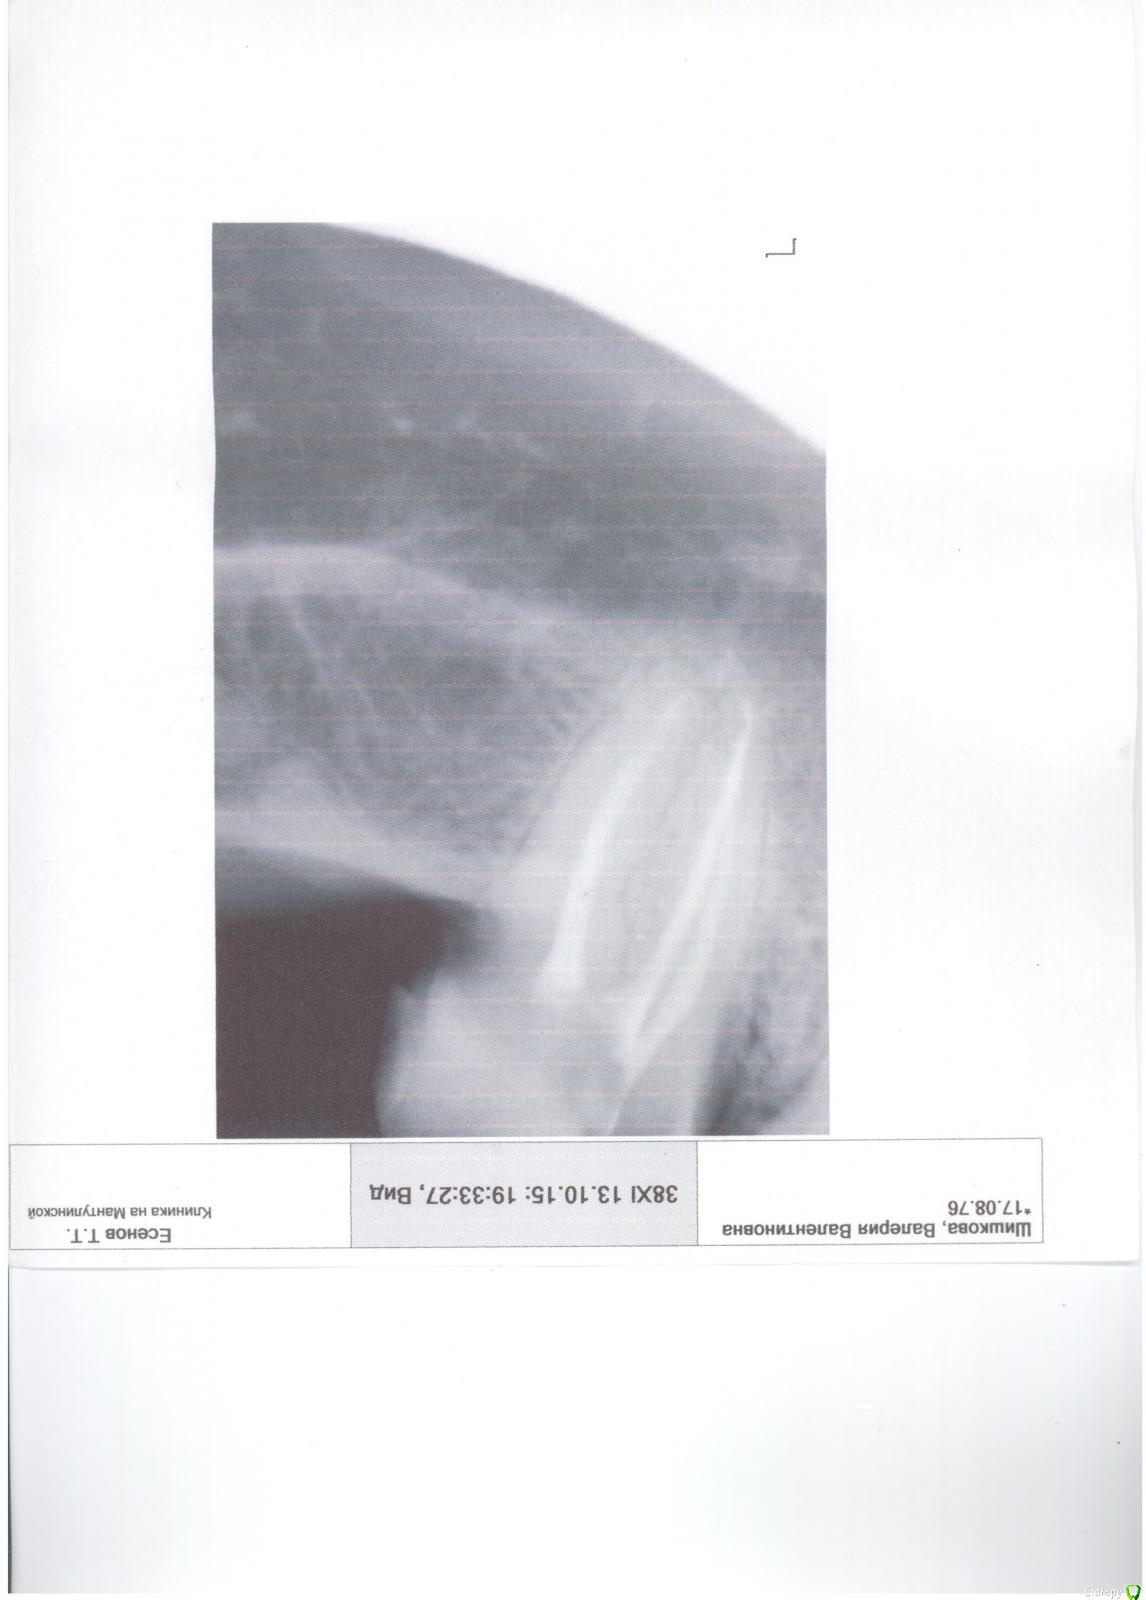

Валерия2 Опубликовано 16 октября, 2015 Поделиться Опубликовано 16 октября, 2015 (изменено) Посоветуйте,что делать, совсем запуталась. У меня неделю назад разрушилась пломбы 7 нижнего зуба, а также его внутренняя стенка обломилась. Была у нескольких врачей-ортопедов в платных клиниках, мнение у них сошлось на том,что необходимо делать вкладку и на нее коронку. Все говорили,что работа сложная,нет никакой гарантии. Сегодня зашла со снимком в районную -Он посмотрел на снимок,и сказал ,что так как корни без трещин (возможно дословно я неправильно пишу,но так как поняла)и соединены ложем,то здесь нельзя ставить вкладку,так как при обтачивании под вкладку пройдут это нижнее ложе и корни разойдутся,тогда только под удаление. Теперь совсем не знаю ,что делать,какое решение принять, очень хочу сохранить этот зуб,подскажите. Причем один из врачей меня предупредил,что если мне предложат сделать коронку - не делайте,совсем зуб потеряете. И тем не менее ...внушает мне доверие, он говорит,что делать нужно только металл,так как под него совсем мало снять придется.Прикрепляю снимок Изменено 16 октября, 2015 пользователем IvanK Ссылка на комментарий

Валерия2 Опубликовано 16 октября, 2015 Автор Поделиться Опубликовано 16 октября, 2015 есть снимок, который выложила - он распечатан на бумаге, сегодня заберу ренген -выложу(делали на пленке, как раньше/ маленький, наверно только панорамный подойдет что-либо понять?) Ссылка на комментарий

Валерия2 Опубликовано 16 октября, 2015 Автор Поделиться Опубликовано 16 октября, 2015 Думаю, как сделать фото, сейчас попробую, ситуация визуально такая, защечная стенка есть, и на ней висит часть оставшейся пломбы, внутренняя стенка обломана, облом уходит вниз под десну, так вот, врачи платных клиник утверждают,что так как разрушение более 50%, то только вкладка (но не дают вообще никакой гарантии-обошла троих, и ,честно говоря меня интуитивно останавливает их быстрый диагноз) в районной доктор,посмотрев, сказал,как я уже писала выше, объяснил,что он бы не взялся делать вкладку,так как велика вероятность надлома ложа,а делать нужно только металлическую коронку. Я задала вопрос, будет ли к чему прикрепить коронку, так как внутренняя стенка сломана неизвестно где, он говорит-это наши проблемы,укрепить можно, но только металл, так как мало сточим. Извините, просто вопрос для меня животрепещущий. Я почему в районную пошли, денег я готова заплатить, но за хорошую работу, а если тебе говорят,что нет гарантии(то есть врач страхуется заранее,так я понимаю, а если что скажет, ну я же предупреждал..) сейчас попробую фото сделать. Спасибо ,что пытаетесь помочь) Ссылка на комментарий

Валерия2 Опубликовано 16 октября, 2015 Автор Поделиться Опубликовано 16 октября, 2015 Спасибо за ответ. скажите, а возможно поставить коронку без вкладки. я так понимаю,что коронка крепится на штифты (ну как раньше делали+ мет коронка) . Я не имею в виду технически, скорее всего возможно, а насколько долговечно. Врач сказал,что простоит сколько сам зуб простоит и объяснил так, что когда начнут каналы проходить для вкладки, их расширят и возможно сломают перемычку между корнями- тогда только под удаление (видимо по снимку он увидел,что она истончена) , а все врачи помоложе - за вкладку, причем мне сказали неразборную, -будут вводить в 2 канала. Ссылка на комментарий

IvanK Опубликовано 16 октября, 2015 Поделиться Опубликовано 16 октября, 2015 Коронка одевается на "что-то", а у Вас почти весь зуб состоит из пломбы, а другая часть откололась... Если скол ниже уровня десны, то перспектив у зуба не много. . Ссылка на комментарий

DR.P Опубликовано 16 октября, 2015 Поделиться Опубликовано 16 октября, 2015 В вашем случае если судить по предоставленным фотографиям, только вкладка + коронка. Но хочется увидеть на сколько глубоко с язычной стороны. Ссылка на комментарий